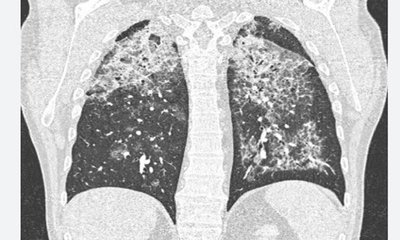

ಬೆಂಗಳೂರು: ಮೇಲ್ನೋಟಕ್ಕೆ ಸಾಮಾನ್ಯ ವೈರಲ್‌ ನಿಮೋನಿಯಾ ಕಾಯಿಲೆ ಲಕ್ಷಣ ಹೊಂದಿದ್ದ ಮಹಿಳೆಯಲ್ಲಿ, ತಪಾಸಣೆ ಬಳಿಕ ಅತಿ ಅಪರೂಪದ ಕಾಯಿಲೆಗಳಲ್ಲಿ ಒಂದಾದ ಶ್ವಾಸಕೋಶದ ಗಾಳಿ ಚೀಲದಲ್ಲಿ ಅಸಾಮಾನ್ಯವಾಗಿ ಸಂಗ್ರಹವಾಗುವ ಪ್ರೊಟೀನ್‌ ನಿಂದುಂಟಾಗುವ ಕಾಯಿಲೆ "ಪಲ್ಮನರಿ ಅಲ್ವಿಯೋಲಾರ್‌ ಪ್ರೊಟಿನೋಸಿಸ್‌" ಪತ್ತೆ ಹಚ್ಚಿದ ಸ್ವರ್ಶ್‌ ಆಸ್ಪತ್ರೆ ವೈದ್ಯರ ತಂಡ, ಸಂಪೂರ್ಣ ವಾಗಿ ಗುಣಪಡಿಸುವಲ್ಲಿ ಯಶಸ್ವಿಯಾಗಿದ್ದಾರೆ.

ಈ ಕುರಿತು ಮಾತನಾಡಿದ ಡಾ. ವಿವೇಕ್‌ ಗುಂಡಪ್ಪ, ಉಸಿರಾಟದ ಸಮಸ್ಯೆಗಳು ಗಂಭೀರವಾದಾಗ ಮೊದಲು ನಿಮೋನಿಯಾ ಇರಬಹುದು ಎಂದೇ ಭಾವಿಸಲಾಗುತ್ತದೆ. ಇದೇ ರೀತಿಯ ರೋಗಲಕ್ಷಣ ಗಳಾದ ದೀರ್ಘಾವಧಿ ಕಫ, ಉಸಿರಾಟ ಸಮಸ್ಯೆ, ನಿರಂತರ ಆಯಾಸದಿಂದ ಬಳಲುತ್ತಿದ್ದ 39 ವರ್ಷದ ಮಹಿಳೆಗೆ ಮೊದಲು ವೈರಲ್‌ ನಿಮೋನಿಯಾ ಸೋಂಕಿನ ರೋಗ ಪತ್ತೆ ಮಾಡಲಾಗಿತ್ತು, ಹಲವು ಸುತ್ತಿನ ವೈದ್ಯಕೀಯ ಚಿಕಿತ್ಸೆಯನ್ನೂ ನೀಡಲಾಗಿತ್ತು. ಆದರೆ ದೇಹದ ಸ್ಥಿತಿ ದಿನೇ ದಿನೇ ವಿಷಮಿಸು ತ್ತಿದ್ದುದರಿಂದ, ವೈದ್ಯರ ತಂಡ ಎಚ್ಚೆತ್ತುಕೊಂಡು, ಎದೆ ಭಾಗದ ಎಕ್ಸ್‌ ರೇ ತೆಗೆದಾಗ ಅತ್ಯಂತ ವಿರಳವಾದ ಚಿತ್ರ ಕಂಡಿತು.

ಅಷ್ಟೆಅಲ್ಲದೆ, ಸಿಟಿ ಸ್ಕ್ಯಾನ್‌ ಮಾಡಿದಾಗ ಇದು ನಿಮೋನಿಯಾ ಅಲ್ಲವೆಂಬುದು ವೈದ್ಯರಿಗೆ ಖಾತ್ರಿ ಆಗಿತ್ತು. ಶ್ವಾಸಕೋಶದ ಚಿತ್ರಣ ಪತ್ತೆಗೆ ಬ್ರಾಂಕೋಸ್ಕೋಪಿ ನಡೆಸಿದಾಗ ಶ್ವಾಸಕೋಶದಲ್ಲಿನ ದ್ರವ ಹಾಲಿನ ರೂಪದಲ್ಲಿದ್ದುದು ಕಂಡು ಬಂದಿತ್ತು. ಇನ್ನೂ ಹೆಚ್ಚಿನ ವಿಶ್ಲೇಷಣೆ ನಡೆಸಿದಾಗ ಪಲ್ಮನರಿ ಅಲ್ವಿಯೋಲಾರ್‌ ಪ್ರೊಟಿನೋಸಿಸ್‌ (ಪಿಎಪಿ)ಎಂಬುದು ಖಾತರಿ ಆಗಿತ್ತು. ಪ್ರೋಟೀನ್‌ ನಂತಹ ವಸ್ತು ದಟ್ಟವಾಗಿ ಶ್ವಾಸಕೋಶದಲ್ಲಿ ಸಂಗ್ರಹವಾಗಿ ಶ್ವಾಸಕೋಶದ ಸಾಮಾನ್ಯ ಕ್ರಿಯೆಯನ್ನು ಇದು ಅಡ್ಡಿಪಡಿಸುತ್ತಿತ್ತು. ತಕ್ಷಣ ಕಾರ್ಯ ಪ್ರವೃತ್ತರಾದ ನಮ್ಮ ತಂಡ, ಶ್ವಾಸಕೋಶವನ್ನು ಮೊದಲಿಗೆ ಸಂಪೂರ್ಣವಾಗಿ ತೊಳೆದು ಸ್ವಚ್ಛಗೊಳಿಸಿದರು. ದೇಶದ ಕೆಲವೇ ಆಸ್ಪತ್ರೆಗಳಲ್ಲಿ ಈ ವೈದ್ಯಕೀಯ ಚಿಕಿತ್ಸಾ ಸೌಲಭ್ಯವಿದೆ. 17 ಲೀಟರ್‌ ಉಪ್ಪಿನ ದ್ರಾವಣವನ್ನು ರೋಗಿಯ ಶ್ವಾಸಕೋಶ ಸ್ವಚ್ಛಗೊಳಿ ಸಲು ಬಳಸಿ ಸಂಪೂರ್ಣ ಶ್ವಾಸಕೋಶವನ್ನ ತೊಳೆದು ಶ್ವಾಸಕೋಶದಿಂದ ಹೊರ ಬರುವ ದ್ರಾವಣ ವು ಪೂರ್ಣ ಸಾಮಾನ್ಯವಾಗುವವರೆಗೂ ಈ ಪ್ರಕ್ರಿಯೆ ನಡೆಸಿ ರೋಗಿ ಚೇತರಿಸುವಂತೆ ಮಾಡಲಾಯಿತು ಎಂದರು.